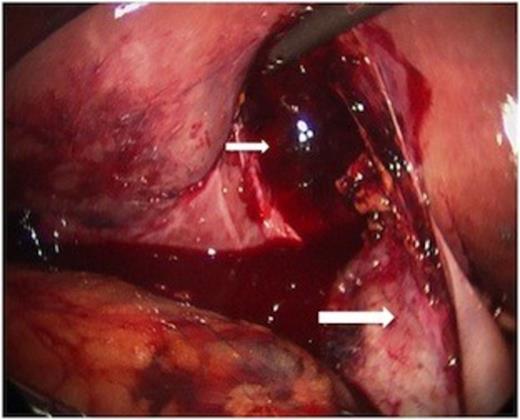

The body of the gallbladder was perforated on its inferior surface (arrow).

Minimal additional blunt dissection exposed the cystic artery and duct. A critical view of safety was achieved so that cholecystectomy could be performed. Only a small amount of oozing was noted from the liver laceration, following removal of the gallbladder. Haemostasis was achieved with topical agents. The pathologic specimen showed acute inflammation with perforation (Figure 4).